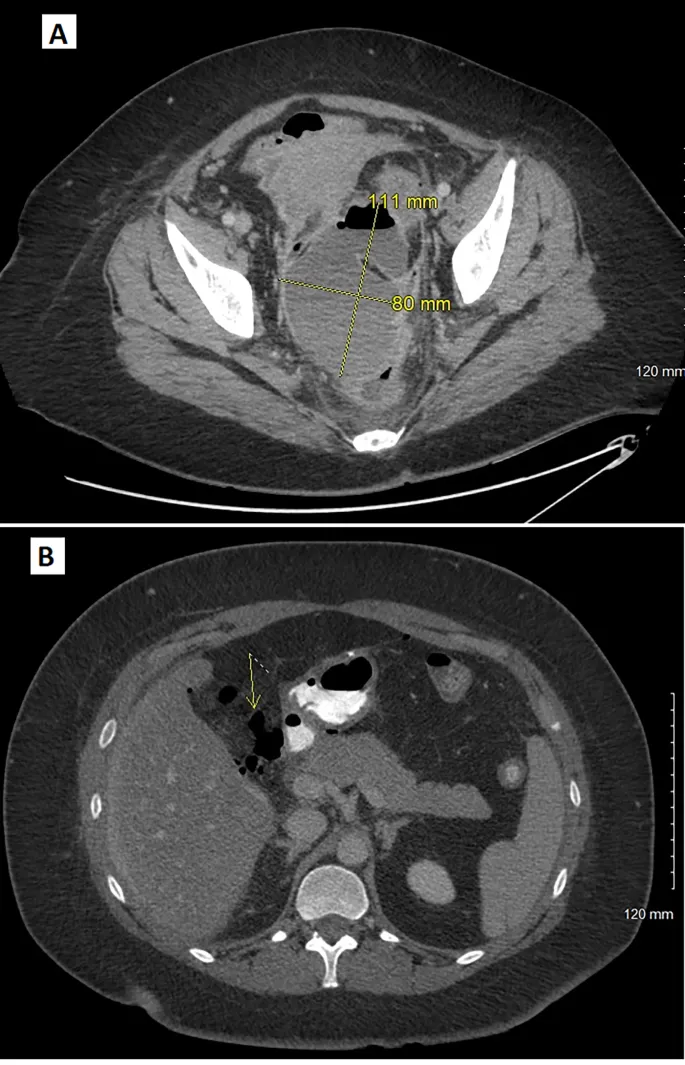

- Concealed: Signs of hypovolemia without obvious loss. Think retroperitoneum, thorax, or pelvis. Presents with tachycardia, hypotension, oliguria.

- Imaging: Bedside FAST scan for quick assessment; CT angiography is gold standard for localizing the bleed.